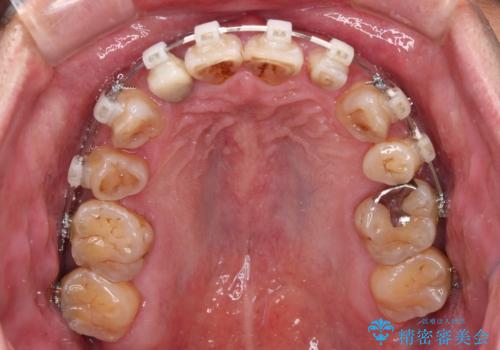

- 矯正装置

- 審美装置

全額的にデコボコが強いため、上下左右の小臼歯計4歯を抜歯し、ワイヤー装置による矯正治療を行うこととしました。

抜歯する歯の一部をセオリーである第一小臼歯ではなく、第二小臼歯にすることで、骨格的なずれをカバーするように計画しました。

小臼歯の抜歯する部位を選択したことで、安定した咬み合わせとなりましたが、第二小臼歯を抜歯した部分はスペースを閉じるのに長い期間を要しました。

矮小歯であった上顎前歯2本は、矯正治療後にバランスの取れた大きさのオールセラミッククラウンを装着しました。